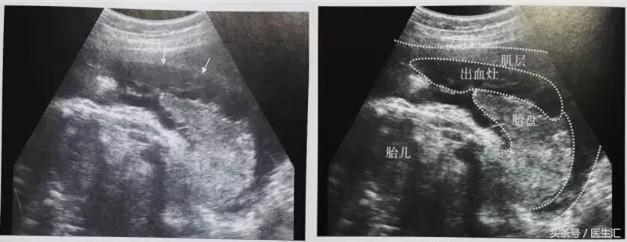

1.胎盘剥离早期:胎盘与子宫壁间见边缘粗糙、形态不规则的液性暗区,其内可见散在斑点状高回声、不均质低回声或杂乱回声,有时为条带状回声(见图6黄色圈内)。有时胎盘后无明显血肿声像,仅有胎盘异常增厚(注意对比历史报告),呈不均增强回声。

(图6)

2.胎盘剥离后期:胎盘剥离出血不多自行停止后,胎盘后血肿数天后逐渐液化,内回声变为无回声,与子宫壁界限分明;以后血肿机化,表现为不均质高回声团,产后检查胎盘局部有机化凝血块。

3.胎盘边缘血窦破裂:胎盘边缘胎膜与宫壁分离、隆起,胎膜下见不均质低回声。(见图7)

(图7)